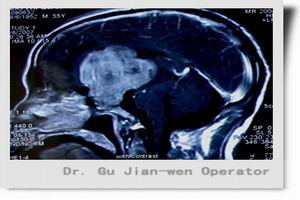

顱咽管瘤是由外胚葉形成的顱咽管殘餘的上皮細胞發展起來的一種常見的胚胎殘餘組織腫瘤,為顱內最常見的先天性腫瘤,好發於兒童,成年人較少見,好發於鞍上。其主要臨床特點有下丘腦-垂體功能紊亂、顱內壓增高、視力及視野障礙,尿崩症以及神經和精神症狀,CT檢查可明確診斷。治療主要為手術切除腫瘤。

診斷:任何年齡的病人如出現高顱壓、神經眼科症狀及下丘腦-垂體功能紊亂均應考慮顱咽管瘤的可能。根據好發部位、臨床表現及輔助檢查診斷顱咽管瘤並不困難。凡青少年兒童出現內分泌功能障礙,如發育矮小、多飲多尿、肥胖、生殖器發育不良等,均應首先考慮本病;若有鞍上或鞍內鈣化斑,更有助於診斷。若成人出現性功能障礙或頭痛、視力視野障礙,也應考慮本病。少數臨床表現不典型者、臨床症狀輕微者診斷不易,關鍵是要提高對本病的警惕性。通過實驗室檢查、CT和MRI對診斷具有重要的意義,對疑似病例應及時做此種檢查,以免延誤診斷。實驗室檢查:普通實驗室檢查無特殊。內分泌功能檢查多數病人可出現糖耐量曲線低平或下降延遲,血T3、T4、FSH、LH、GH等各種激素下降。少數表現為腺垂體功能亢進,大多數表現為程度不等的腺垂體及相應靶腺功能減退。